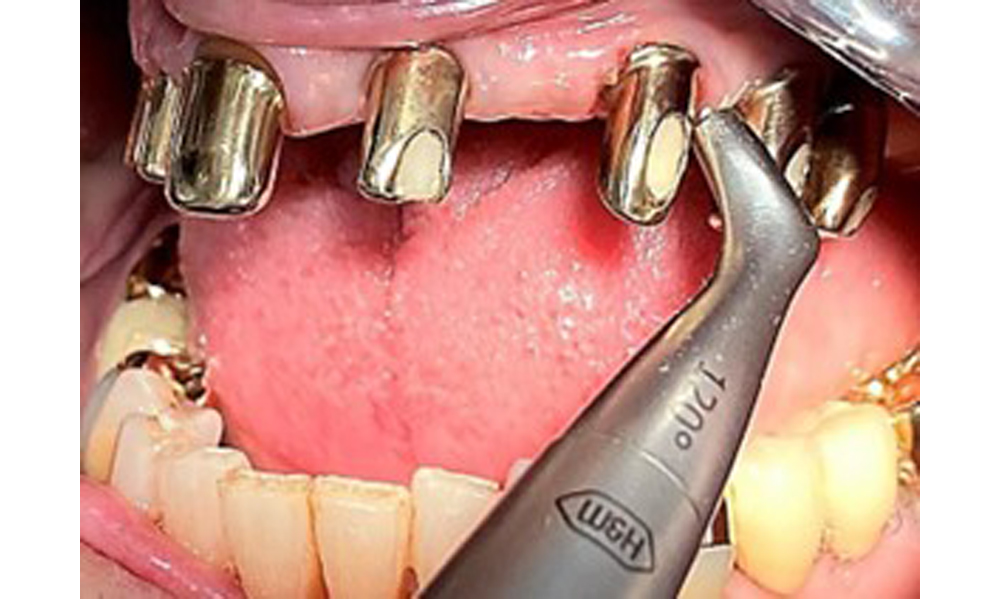

Sonic/ultrasonic, or conventional manual instruments may be used to remove calculus and concretions present on the natural teeth (8). Titanium or plastic curettes (Fig. 10), or a plastic or PEEK attachment (Fig. 11) during ultrasonic treatment, should be used to remove mineralized plaque from implants to avoid damaging the implant surfaces.

The dental findings are as follows: Combined removable implant and tooth-supported telescopic prostheses on implants 15, 13, 21, 23, 24, 25 and tooth 11 (Fig. 1, Fig. 2, Fig. 3). The patient was fitted with a fixed mandibular denture. Adequate bridges were present over 37 to 34 and 45 to 47 (Fig. 4), the crown margins were intact and there were no active caries. A composite filling with a marginal gap was present on tooth 43. There was mandibular gingival recession, exposing 1 to 3 mm of root surface. This also applies to 11.